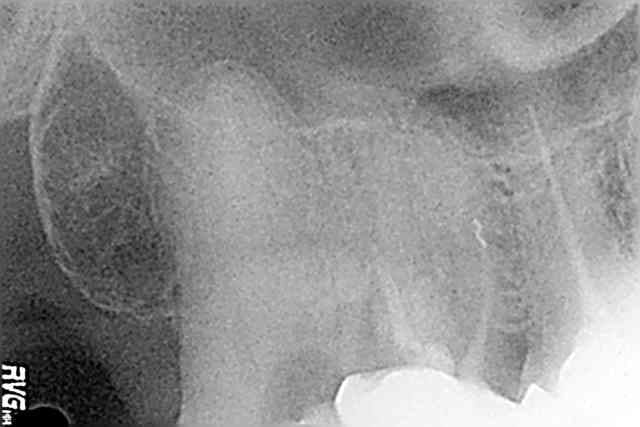

LdL

05/03/2009 à 15h53

Un regret, pas avoir prévu assez de temps pour obturer dans la séance, et ne pas avoir pris le temps de reconstituer la dent à la 3 ème fois ou le clamp a sauté.

'J'Desinfecterai à fond lors de l'obtu... promis???

(les radios sont pas dans le bon ordre, vous aurez rectifié de vous-même...)

Rte houb pre g3nb9d - Eugenol

Rte houb per k8piil - Eugenol